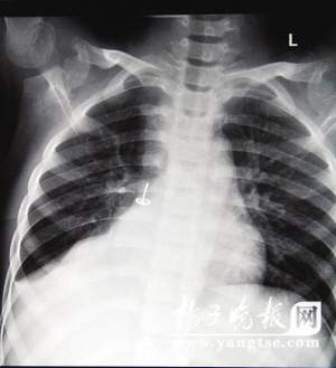

從片子上,圖釘在孩子右肺里“潛伏”得很深,卡在右下葉支氣管。南京市兒童醫(yī)院耳鼻喉科周艾醫(yī)生表示,由于圖釘堵住了孩子支氣管的通道,導致右肺葉不擴張,肺部已經(jīng)發(fā)生了實質(zhì)性的改變,用擴張來進行氧氣交換的肺泡都已經(jīng)“癟”下去了,所以孩子的肺部功能非常弱。從片子上看,孩子的右肺已經(jīng)嚴重“萎縮”,比左肺小了一大圈。